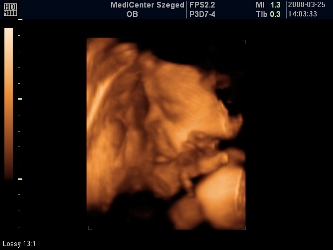

Megjöttünk a 4D-ről! :lol: 40 percet moziztunk, mert Patriknak már a legelején elege lett az egészből, befúrta a fejét a méhlepénybe, rángatta a zsinórt, rúgta a vizsgálófejet, úgyhogy nagyon nem tetszett neki. Azért lett pár kép, de nagyon megsajnáltam a kis drágámat, és én szóltam, hogy mostmár hagyjuk békén. Szerencsére minden a legnagyobb rendben, szép mindene, és befordult (múlt héten még faros volt) és ez a lényeg!!! :lol:

A méretei mostmár bizti, hogy 2 héttel nagyobbak, tehát 30 betöltött hétnek megfelelő, de a vonalzóm mostmár marad, úgyis a bébi dönti el, hogy mikor jön pontosan (de eszerint június 1-én) :lol:

A súlya: 1320 gram :shock:

Rakok képeket: kettő pofis, egy zacsis. :oops: :lol: